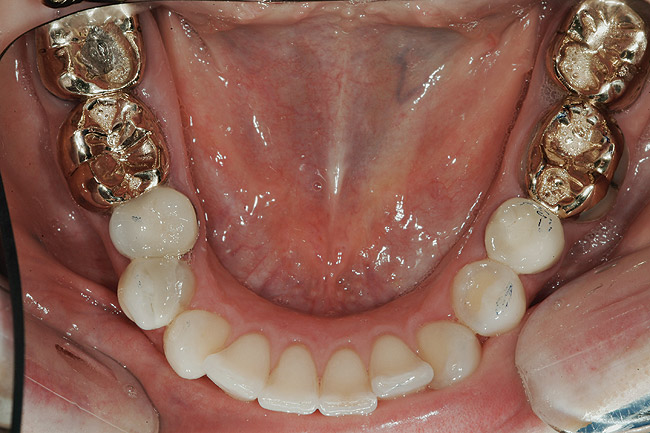

ETAPA aIV-a: RESTAURĂRI MANDIBULARE

S-au finalizat restaurările mandibulare cu utilizarea coroanelor integral ceramice din disilicat de litiu pe dinţii 3.7.-3.5., 4.5. şi 4.6., precum şi o restaurare din compozit a dintelui 3.4. Mai întâi s-a restaurat partea stângă, apoi partea dreaptă a pacientei. La restaurarea fiecărui cadran inferior, s-a folosit deprogramatorul Kois ca punct de referinţă stabil şi repetabil în gestionarea ocluziei.

S-a fabricat o gutieră maxilară nocturnă pentru a proteja porţelanul în scopul gestionării pe termen lung, într-un efort de a face tot posibilul pentru a reduce riscul. Pacienta a amânat tratamentul dinţilor 1.7. şi 4.7., care încă prezintă coroane din aur vizibile şi la dintele 2.7., cu coroană provizorie din compozit.

Deprogramatorul Kois a servit ca un instrument convenabil pentru diagnosticul şi managementul predictibil al cererilor funcţionale prezente. A trecut peste 1 an de când s-a finalizat tratamentul pacientei. Durerile de cap nu i-au revenit şi ea raportează că încleştarea şi scrâşnitul s-au abolit. Este foarte mulţumită de estetica finală (fig. 14-17) şi de rezultatul de succes al cazului (fig. 9). Prognosticul global este îmbunătăţit datorită reducerii riscurilor funcţionale şi biomecanice.